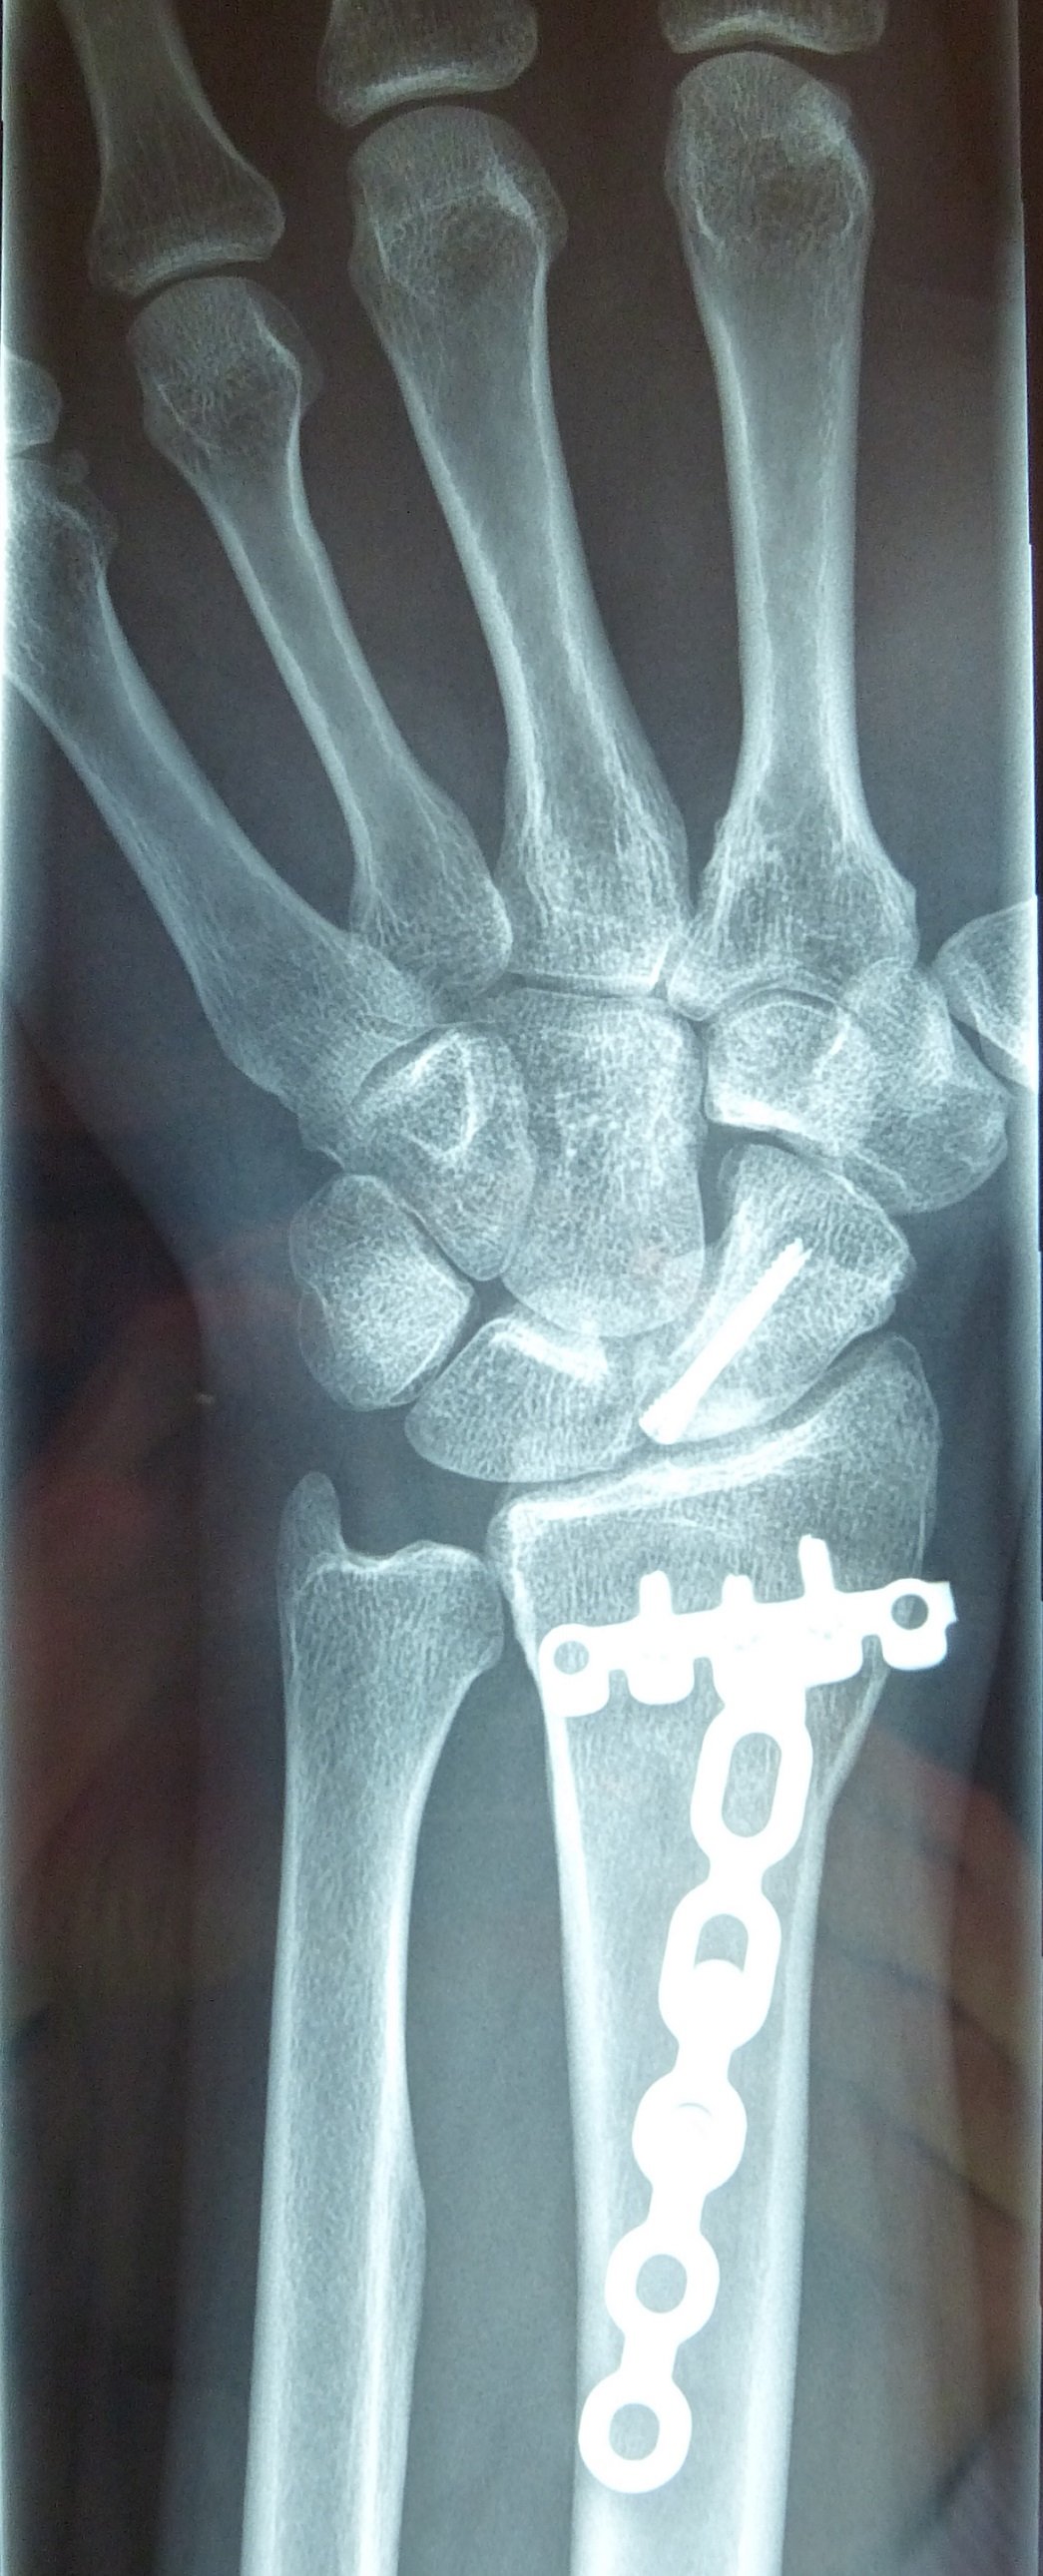

Προεγχειρητικά

Η αντιμετώπιση της ψευδάρθρωσης του σκαφοειδούς είναι πάντοτε χειρουργική. Με ραχιαία ή παλαμιαία προσπέλαση αποκαθίσταται ο άξονας του σκαφοειδούς και σταθεροποιείται το σκαφοειδές με ειδική βίδα ή βελόνες, με παράλληλη τοποθέτηση οστικών μοσχευμάτων. Μπορεί επιπλέον να γίνει και οστεοτομία κλειστής σφήνας του περιφερικού άκρου της κερκίδος. Στις περιπτώσεις άσηπτης νέκρωσης το μόσχευμα πρέπει να είναι αγγειούμενο – για να προσδώσει αιμάτωση στο νεκρωμένο κεντρικό τμήμα – και λαμβάνεται με μικροχειρουργικές τεχνικές από το περιφερικό τμήμα της κερκίδος ή από άλλα τμήματα του σώματος